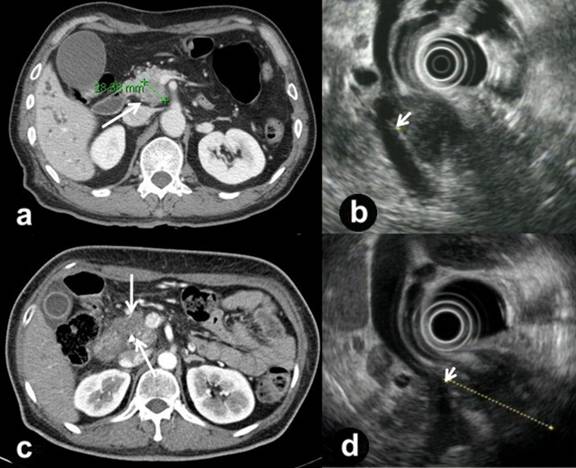

A 68-year-old man presented with epigastric and back pain of 1 month duration. His preoperative CT (Figure 1a) and PET scans revealed a 3.5 cm pancreatic head cancer with suspicious invasion into the portal vein without distant metastasis, and an endoscopic ultrasonography (EUS) showed the portal vein involvement of the tumor in detail (Figure 1b). The serum CEA level was 1.55 ng/mL (reference range: 0-5.00 ng/mL) and the CA 19-9 level was 757 U/mL (reference range: 0-37 U/mL). EUS-guided fine-needle biopsy confirmed an adenocarcinoma of the pancreas. He received neoadjuvant concurrent chemoradiation therapy according to our institutional policy for advanced pancreatic cancer. A partial response was identified on a follow-up study after the concurrent chemoradiation therapy, but vascular involvement was still suspected. We decided to perform a pancreaticoduodenectomy with a possible segmental resection of the superior mesenteric-splenic-portal vein confluence, and left renal vein interposition grafting.

Figure 1. Preoperative imaging studies. a. CT of Case #1 showing pancreatic head cancer (arrow) with suspicious invasion to the portal vein. b. EUS of Case #1 revealing the tumor abutting on the portal vein (arrow). c. CT of Case #2 demonstrating pancreatic head cancer (arrows) invading the superior mesenteric-splenic-portal vein confluence. d. EUS of Case #2 clearly demonstrating the tumor abutting on the superior mesenteric-splenic-portal vein confluence (arrow). |

A 48-year-old woman was admitted with weight loss of one month duration and jaundice of five days duration. Her preoperative CT also demonstrated pancreatic head cancer invading the superior mesenteric-splenic-portal vein confluence (Figure 1c), and mild uptake was identified on a PET scan. EUS clearly showed the 4.0 cm pancreatic head cancer abutting on the superior mesenteric-splenic-portal vein confluence (Figure 1d). The serum CEA level was 3.40 ng/mL and the CA 19-9 level was 660 U/mL. Adenocarcinoma of the pancreas was confirmed by EUS-guided fine-needle biopsy. Neoadjuvant concurrent chemoradiation therapy for advanced pancreatic cancer was carried out, and stable disease was identified on follow-up studies after concurrent chemoradiation therapy.